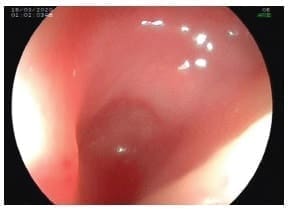

La endoscopia de vías digestivas altas confirmó el diagnóstico a 12 cm de la arcada dental, encontrando un divertículo de 2,5 cm de largo en la cara lateral izquierda, sin alimentos en su interior y sin cambios en la mucosa (Figura 2).

Figura 2. Endoscopia de vías digestivas altas que muestra un divertículo de 2,5 cm de largo en la cara lateral izquierda, sin alimentos en su interior y sin cambios en la mucosa.